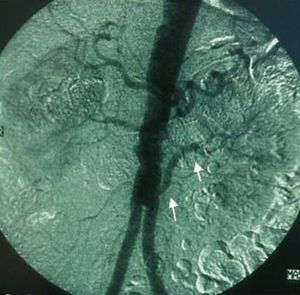

Percutaneous revascularization is the technique of choice in RAS secondary to FMD, with the use of the stent for the treatment of suboptimal dilatations (Figure 8). Restenosis is less common than in atherosclerosis, with an incidence of 8% in a series of 85 cases after a mean follow-up of 15 months.101 In atherosclerosis, the lesions are mostly located in the ostia, with greater elastic recoil. The use is associated with a higher incidence of surgical success, which can reach 98%, and restenosis is less common than in simple angioplasty (17% vs 26%, respectively).102

Figure 8. Percutaneous treatment of renal stenosis (A) with angioplasty and balloon-expandable stent (B) and fibromuscular dysplasia (C) by means of simple balloon angioplasty (D).

Surgical treatment is indicated in the concomitant repair of the aorta due to aortoiliac or aneurysmal occlusive disease, adverse anatomy or involvement of the complex renal arteries (aneurysms, polar arteries, segmental artery lesions), failed percutaneous revascularization or the impossibility of treating restenosis by percutaneous techniques. Revascularization can be carried out by means of endarterectomy (renal or transaortic), aortorenal bypass or extraanatomic bypass (hepatorenal or splenorenal), reimplantation, autotransplantation, or ex vivo surgery for the repair of segmental arteries. The hypertensive kidney with renin hypersecretion may require nephrectomy. The mortality observed in surgical treatment is influenced by the comorbidities associated with atherosclerosis, as well as the complexity of the reconstruction, and is higher in combined aortorenal surgery (Figure 9). Hansen and Dean105 reported an operative mortality of 5.3% in patients undergoing combined surgery, as compared to 1.7% and 0.7% in procedures limited to the renal artery and aorta, respectively. Weibull et al106 randomized 58 patients to surgical or percutaneous treatment, with equivalent results in terms of survival and blood pressure control. In Spain, the progressive disuse of revascularization surgery in favor of percutaneous procedures has resulted in the circumstance that the former is being performed in increasingly fewer centers.

Figure 9. Example of left aortorenal bypass (arrows) in an aortobifemoral revascularization procedure to treat Leriche syndrome.